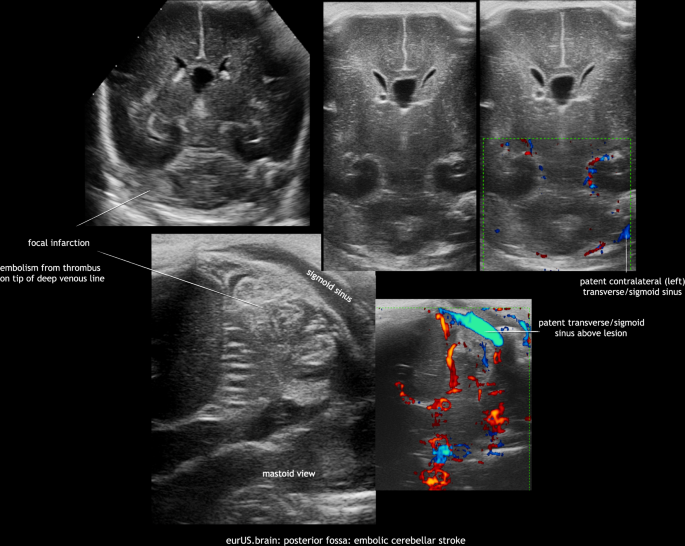

Neonatal bacterial meningitis may be complicated by arterial or venous cerebral infarction. Lesions are often located supratentorially, but have also been described within the cerebellum, especially in cases with group B Streptococcus meningitis. In the acute phase this may appear as increased echogenicity of the involved cerebellar structures on ultrasound. It may progress to destruction and atrophy on follow-up imaging.7 Bacterial meningitis can be complicated by an impairment of cerebrospinal fluid flow and hydrocephalus. In some cases, this occurs in combination with a dilated or isolated fourth ventricle. Brain abscess is an uncommon but very serious complication of newborn central nervous system infections; most are located supratentorially. However, a few cases with cerebellar abscesses have been reported, often in preterm infants with, that is, Staphylococcus aureus or disseminated fungal infections. Most were studied by CT or MRI, but CUS may also be a valuable tool to detect these lesions.9,20 Their sonographic appearance varies depending on organism and evolution with time. Typical findings include single or multiple round hypoechoic lesions surrounded by hyperechoic borders. Embolic focal infarcts may or may not be infected (Figs. 9 and 10).